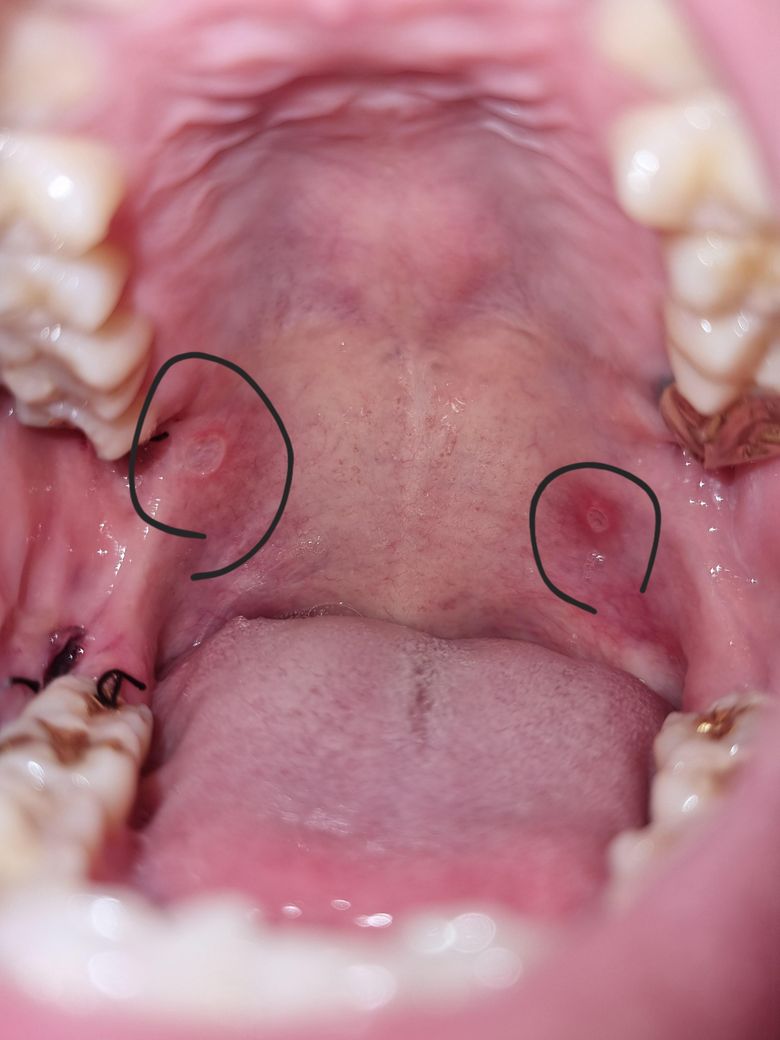

요즘 사랑니발치.목감염으로인해 항생제를 일주일이상 복용중인데 입천장구내염이생긴것같은데 칸디다증초기인가요? 이비인후과 전문의선생님 도와주세요

• 1번 째 사진

칸디다증을 의심할 정도는 아닌 듯 한데 정확한건 진료 봐 보셔야 해요

사랑니를 뽑고 항생제를 사용한 후 구내염과 입 건조, 텁텁한 느낌이 발생하는 것은 칸디다증을 포함한 여러 원인으로 발생할 수 있습니다. 항생제를 많이 사용하면 장내 유익균이 줄어들어 곰팡이균인 칸디다균이 과다 증식할 수 있고, 이로 인해 입안에 하얗고 부드러운 병변이 생길 수는 있죠. 칸디다증은 일반적으로 입안의 하얀 점막 위에 표면적으로 나타나는 경우가 많지만, 구내염과 입 건조는 칸디다 외에도 다른 원인으로 발생할 수 있습니다.

우선 구강 위생을 관리하고 수분을 자주 섭취하는 것이 중요합니다. 만약 증상이 지속되거나 칸디다증을 의심할 수 있는 하얀 병변이 계속된다면 이비인후과나 구강내과를 방문하여 정확한 진단과 치료를 받는 것이 좋습니다.